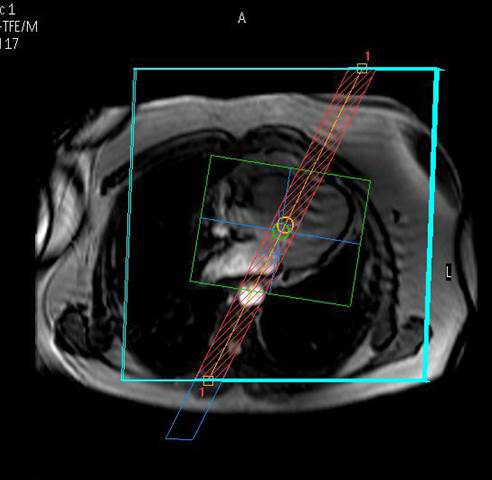

Wir bieten modernste MRT-Diagnostik.

Ganzkörper MR System - Philips healthcare